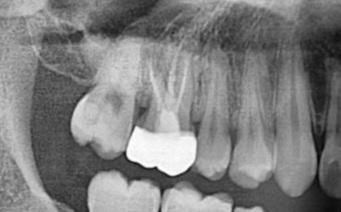

엑스레이는 25년 2월 촬영본입니다!

• 2번 째 사진

엑스레이 상으로는 충치가 없는것같습니다. 인접면에 초기 충치가 잇는거 같으니 일단은 관리를 잘하시는게 중요할것같습니다.

충치가 의심되긴 합니다 치과가서 파노라마 큰 엑스레이 사진 말고 작은 치근단 사진 찍어보세요

현재 사진만으로는 인접면에 대한 정확한 평가가 어렵습니다. 보여주신 x-ray는 panorama 사진으로 전체적인 치아 사진을 보는 것이지 개별적인 치아 상태는 standard view라고 하여 따로 촬영을 해야 합니다. 아래에 찍은 사진만으로도 정확한 판단은 어렵습니다. 가까운 치과 방문 후 x-ray 촬영을 하는 것이 필요해보입니다.